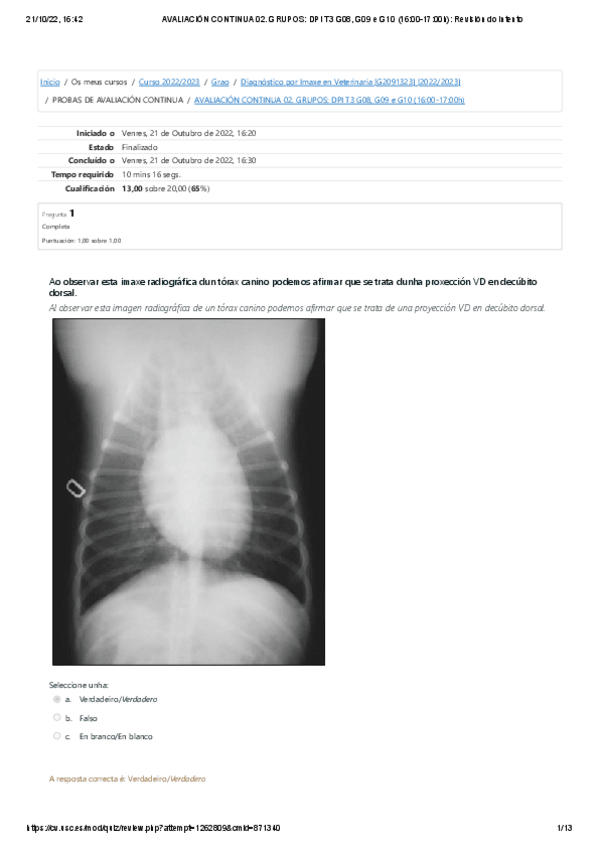

Exámenes - AVALIACION-CONTINUA-02-21-10-2022.pdf